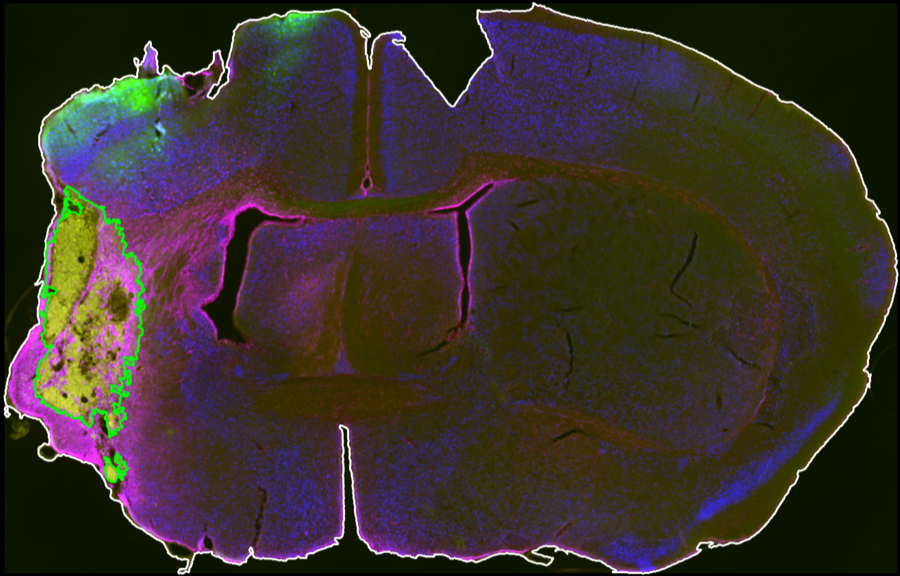

Segmentation Workflow

A GUI with interactive controls defines midline placement, brain contour thresholds, CD68 thresholds, and exclusion-channel thresholds for section-level infarct segmentation.

Outputs

Analysis outputs include segmented infarct masks, merged review images, and CSV summaries saved per animal for quantitative comparison.